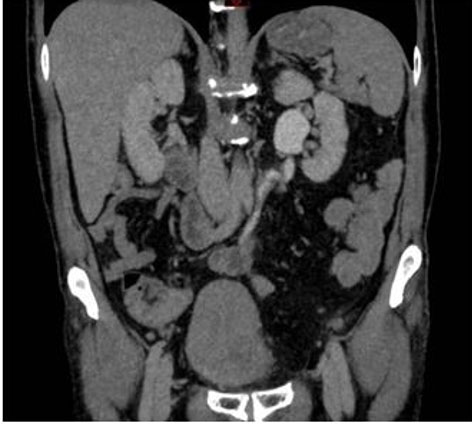

Figure 3: Two months CTU.

A follow-up computed tomography urography (CTU) was performed two months after the surgery, confirming the absence of urinary fistula and the good vascularization of the appendix (Figure 3 and Figure 4).